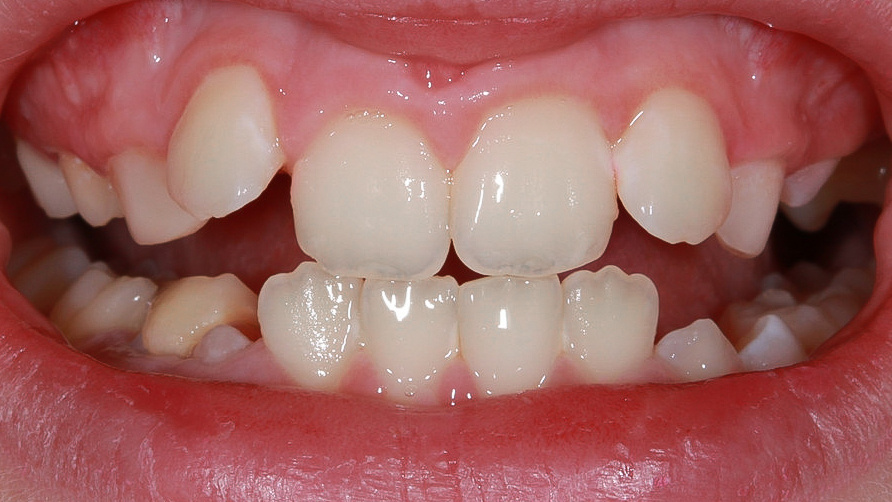

У Алины есть тенденция к глубокому прикусу. Сейчас, пока у девочки еще сменный прикус, можем отслеживать ситуацию и корректировать положение зубов, которые уже прорезались🧐

Рост нижней челюсти ограничен неправильным положением верхних зубов

Основная задача ортодонтического лечения:

✅создать условия, чтобы подросла нижняя челюсть

✅расширить верхний зубной ряд за счет изменения наклона зубов

✅изменить положение передних зубов на верхней челюсти

Для решения этих задач лучше всего подходило лечение на частичной брекет-системе 2х4. В этот же день заказали брекеты и записали Алину на фиксацию системы через неделю.